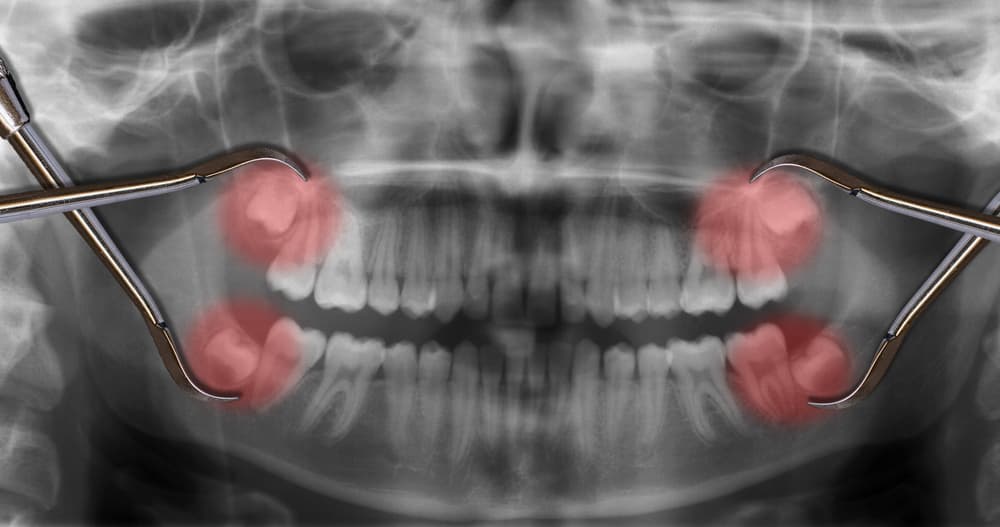

Esto es todo lo que necesitas conocer sobre la extracción de las muelas de juicio

Las personas podemos clasificarnos en tres grupos: aquellas que la pasaron muy muy mal cuando les extrajeron sus muelas de juicio, aquellas que dicen no haber sentido nada y las más envidiadas, aquellas a las que nunca les salieron.